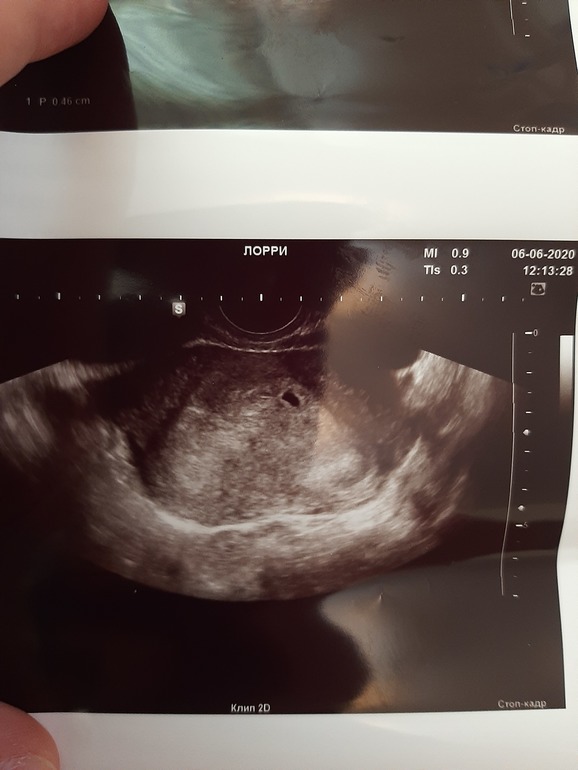

Я не выдержала и сегодня съездила на УЗИ!

МАТОЧНАЯ😍🤭:

✔ПЯ - 4 мм

✔акушерский срок 5+1

✔ по УЗИ 3-4 недели

Но на УЗИ, меня напугали, что двурогая матка, это плохо... почему именно плохо не поняла...